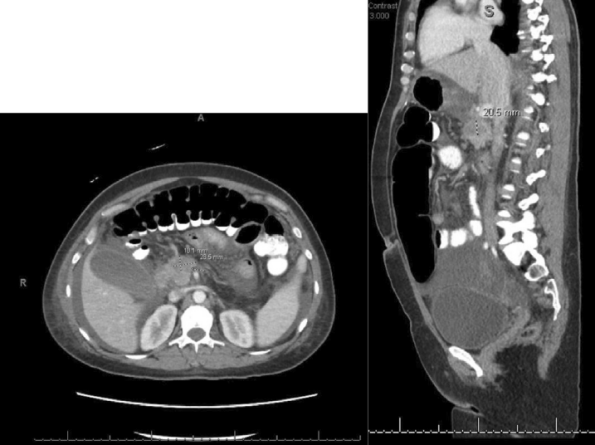

行腹盆腔 CT 扫描,显示间隔性肠容量增大。腹部超声显示和年龄相关的不显著总胆管扩张(图 1),腹腔积液。

图 1. 腹部超声 [1]